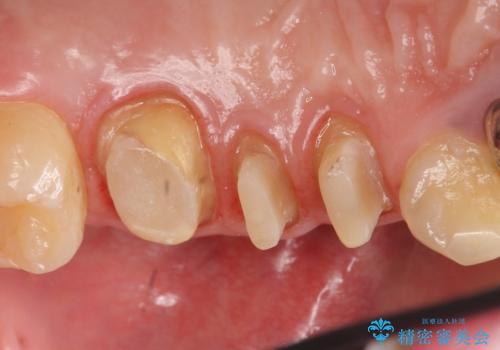

銀歯を除去したところ歯茎よりも深い位置まで虫歯があったため、歯冠長延長術(歯周外科)を行いました。

歯冠長延長術(歯周外科)について

虫歯が進み歯茎より深くなってしまうと、虫歯を取り残してしまうリスク、樹脂の硬化の妨げ、補綴物の不適合、歯肉炎・歯周病のリスクの増大等様々な弊害が起こり得ます。

そのため当院では歯周外科手術(歯茎を下げる手術)や歯の挺出による、虫歯が歯茎より深いという問題の解決を推奨しております。